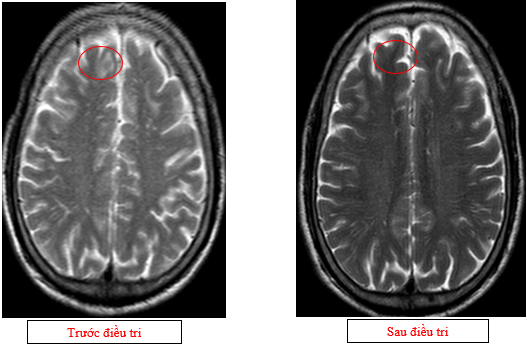

-         Chụp cộng hưởng từ sọ não (11/2025):Nhu mô não hình dạng và cấu trúc bình thường, tín hiệu đồng nhất, ranh giới chất trắng và chất xám rõ. Không thấy tổn thương khu trú hoặc lan tỏa

Hình 13: Không còn thấy tổn thương di căn não vùng bán cầu tiểu não sau điều trị trên phim chụp

Hình 14: Không còn thấy tổn thương di căn não vùng thùy đỉnh sau điều trị trên phim chụp

+      Trên phim chụp cộng hưởng từ sọ não: không còn ghi nhận các ổ tổn thương di căn di não, phù não.